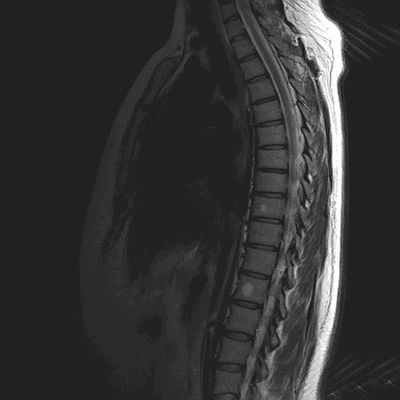

Гемангиомы на магнитно-резонансной томографии грудного отдела позвоночника (сагиттальная проекция, Т2 взвешенная последовательность)

МРТ грудного отдела позвоночника (сагиттальная проекция, Т1 ВИ)